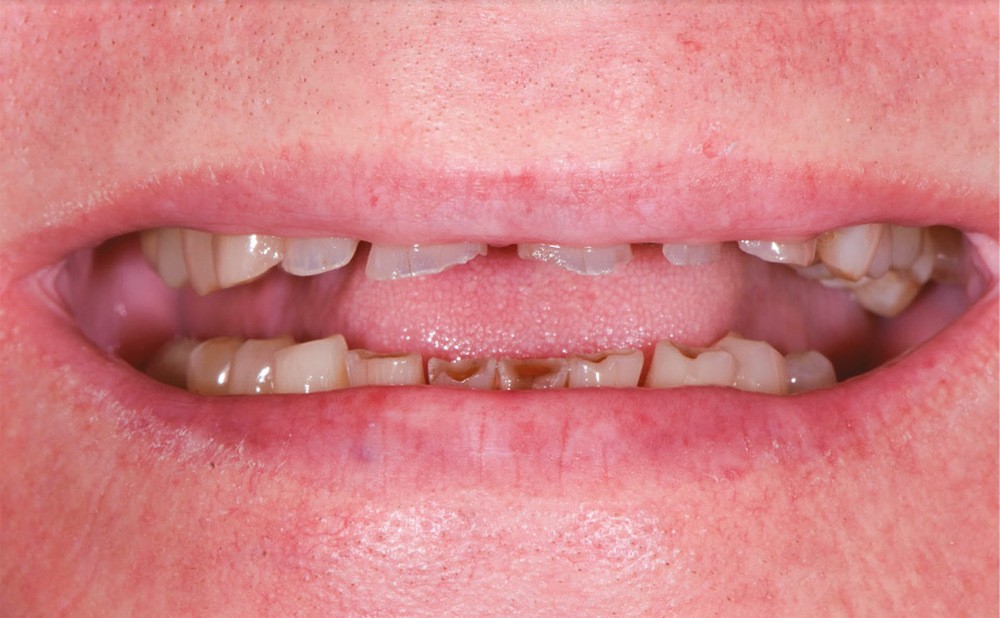

Un patient âgé de 69 ans se présente en consultation pour des problèmes d’ordre fonctionnel et un sourire dégradé. Selon l’adage de Peter Dawson, « l’esthétique et la fonction vont main dans la main », ce cas clinique illustre une situation instable et dysfonctionnelle qui ne sera résolue qu’avec une réhabilitation de la fonction et de l’esthétique (fig. 1 et 2).